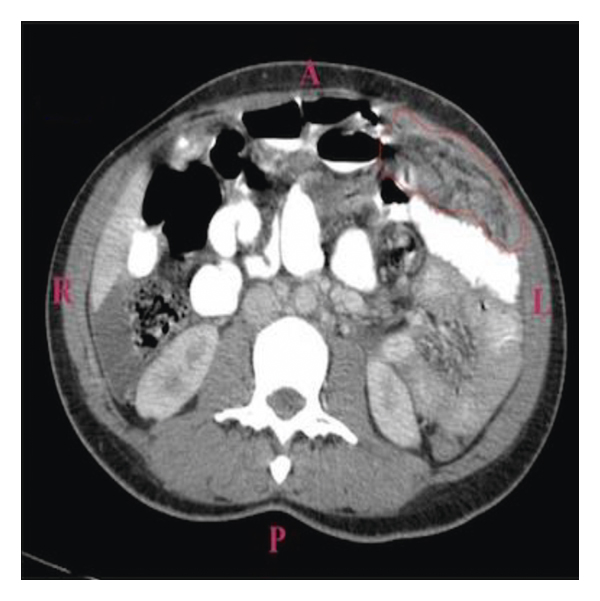

A 38-year-old Liberian female with a 12-week gestation presented to the emergency department with a 3-week history of low-grade subjective fever, night sweats, unintentional weight loss, gradually worsening abdominal pain, and intermittent spotting. Vital signs were stable on presentation, physical exam noticeable for gravida abdomen, otherwise unremarkable. Laboratory examination revealed beta hCG 118471, which was otherwise unremarkable. Pelvic ultrasound confirmed a 12-week viable intrauterine pregnancy. The patient was admitted to the hospital for close monitoring. Hospital course was complicated by massive pleural effusion, low-grade fever, progressive worsening abdominal pain, and spontaneous abortion. Non-contrast-enhanced computed tomography of the chest (Figure 1) revealed large right-sided pleural effusion, and contrast-enhanced computed tomography of the abdomen and pelvis (Figure 2) revealed bilateral hilar adenopathy, ascites, thickening and enhancement of the peritoneum, and mottled nodular-appearing soft tissue consistent with omental caking suspicious for peritoneal carcinomatosis. She underwent extensive workup including surgical and oncologist consultations for possible exploratory laparotomy and discussion of treatment options for presumed ovarian neoplasm. Blood work revealed elevated carbohydrate antigen (CA) 125 and positive QuantiFERON-TB Gold, but adenosine deaminase, CA 19, alpha-fetoprotein, and inhibin B were within normal limits. Diagnostic laparoscopy with biopsy revealed significant pelvis ascites and diffuse miliary lesions throughout the peritoneum. She underwent dilatation and curettage; histopathologic examination showed chronic granulomatous inflammation with no evidence of neoplasm. Special stains on tissue sections and ascitic fluid stain revealed rare acid-fast bacilli, suggestive of mycobacterial granulomatous peritonitis. Additional questioning indicated a history of positive PPD skin test a year prior without follow-up treatment. The patient was placed on four-drug anti-tuberculous therapy and had a complete recovery.